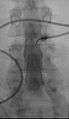

Myelography punction

Conventional myelography in oblique projection. You can see the individual nerve root sheaths.